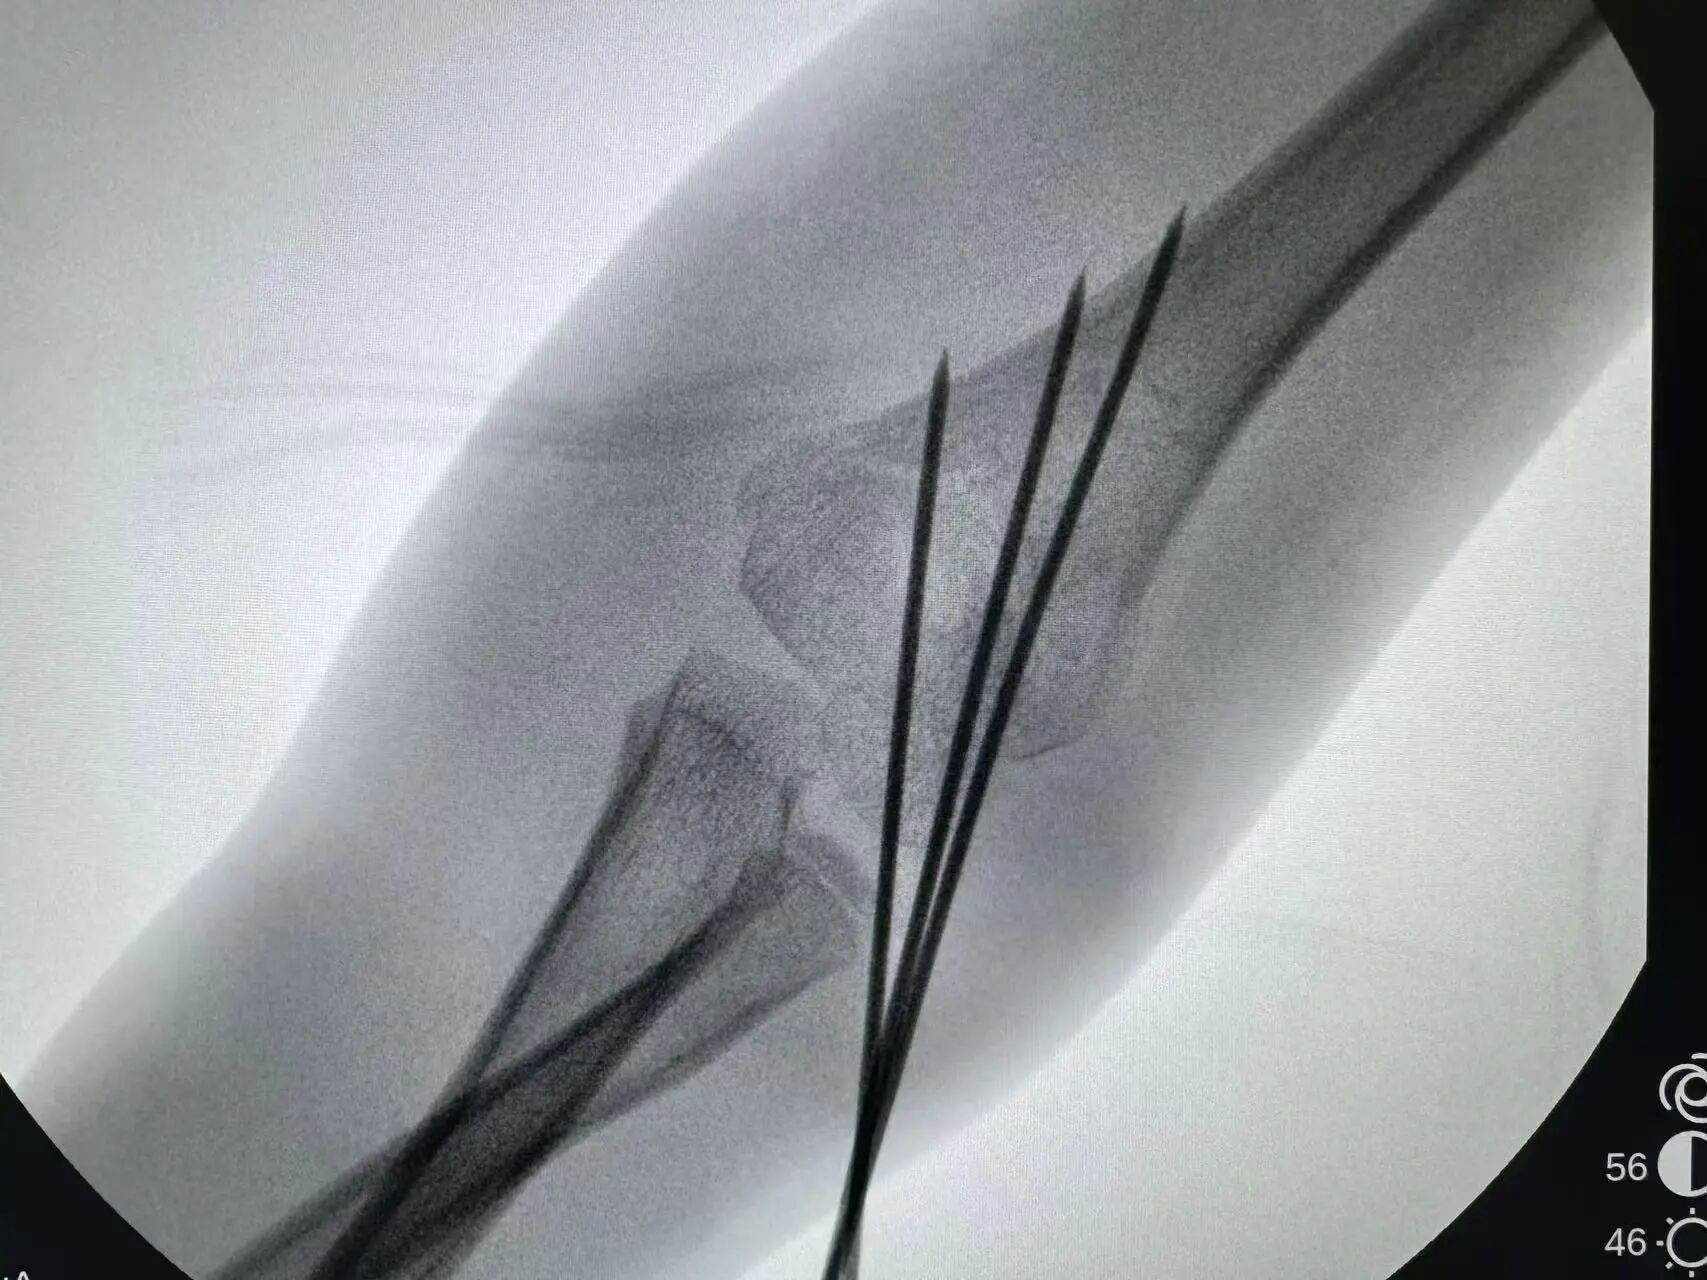

同样“抢时间”的还有小罗和小周的治疗:4岁小罗9月15日深夜入院,10小时后顺利手术;7岁小周同一晚受伤,也在10小时内完成肱骨髁上骨折闭合复位经皮固定术。6岁小郑更是创下“4小时极速手术”纪录——早晨7点40分受伤,8点多入院,11点多手术结束,当天下午就能躺上网课。

“我们的目标是‘24小时内完成急诊手术’,尽量让孩子少耽误一节课。”骨伤科手外·儿骨·烧伤整形组主任陈孝均教授介绍,为了实现这个目标,团队制定了专属流程:孩子入院后,急诊优先开具检查单,放射影像科快速出片;骨科医生同步评估病情,确定手术方案;麻醉科提前做好准备,只要术前检查合格,立刻安排手术——哪怕是深夜或周末,团队也随时待命。

这种“加速度”不仅为学习抢时间,更符合儿童骨折治疗的“黄金原则”:“儿童骨骼生长快,早期复位固定能减少畸形风险,恢复也更快。”陈孝均补充道。